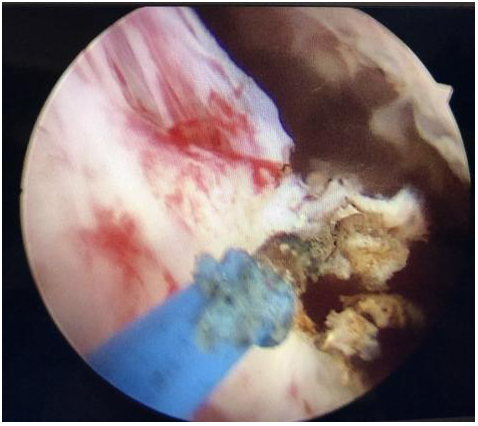

粉碎剜除前列腺組織

81歲的鐘某,因進(jìn)行性排尿困難1年加重3月入院。經(jīng)過系統(tǒng)而完善的檢查,考慮到增生的前列腺體積較大,泌尿外科治療團(tuán)隊為其施行經(jīng)尿道前列腺1470nm激光剜除術(shù)。術(shù)中切除了近180g前列腺(正常前列腺約20g),術(shù)后即刻恢復(fù)排尿,且排尿順暢。